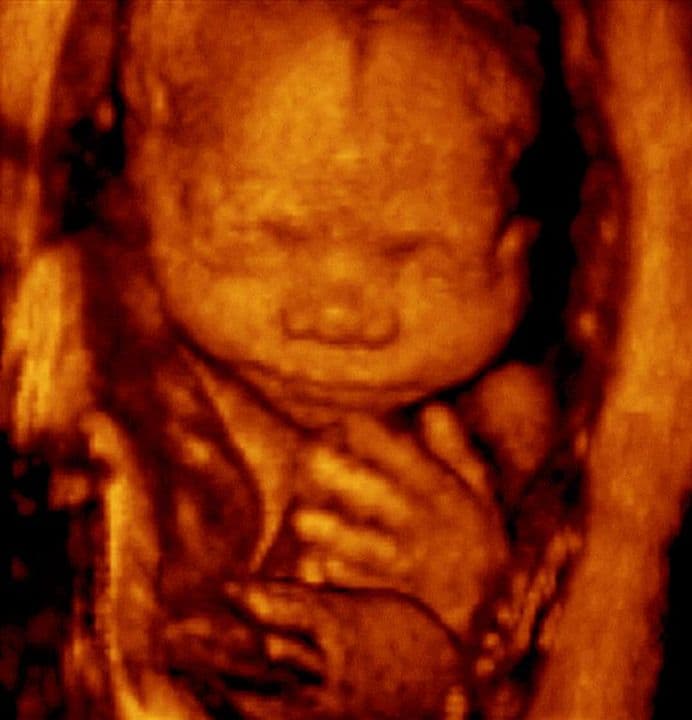

25 weeks and 7 days pregnant

The space between the two frontal bones of the forehead (the dark line) has now nearly closed. The bones on the left and right sides come to lie very close to each other with a small gap to allow for further growth of the head and brain.